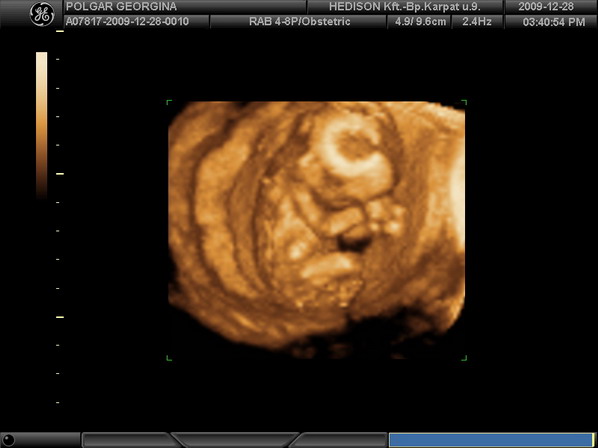

Cikk a Cosmopolitanben Az egér mutatja a fütyijét

Az egér mutatja a fütyijét

Bújós kis baba

Bújós kis baba

Kezd elszunnyadni

Kezd elszunnyadni

Keresztbe tett kéz és törökülés

Keresztbe tett kéz és törökülés

Integet

Integet

Szundika

Szundika

Babatekercs

Babatekercs